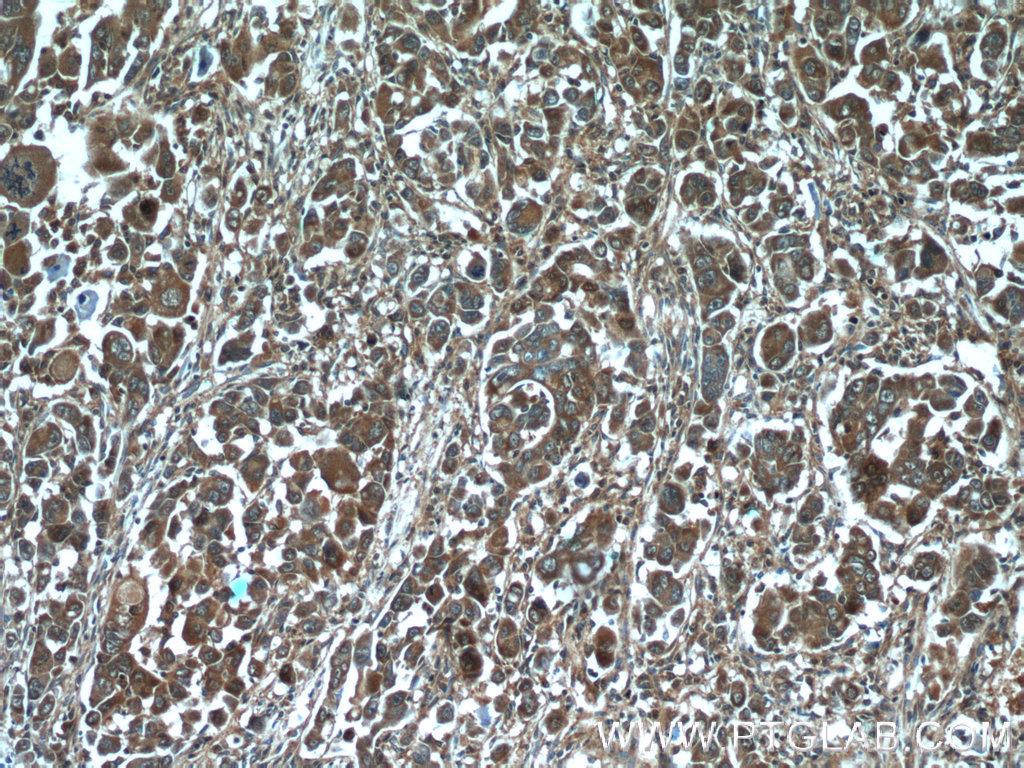

HMGCR抗体

产品名称: HMGCR抗体

英文名称: HMGCRAntibody

产品编号: XY13533-1

使用范围: WB,ELISA,IHC-P,IHC-F,IF

HMGCR抗体